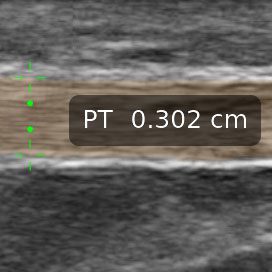

Elevate your sports medicine practice with high-definition dynamic imaging of muscles, joints, and tendons for accurate diagnostics and guided interventions on and off the field.